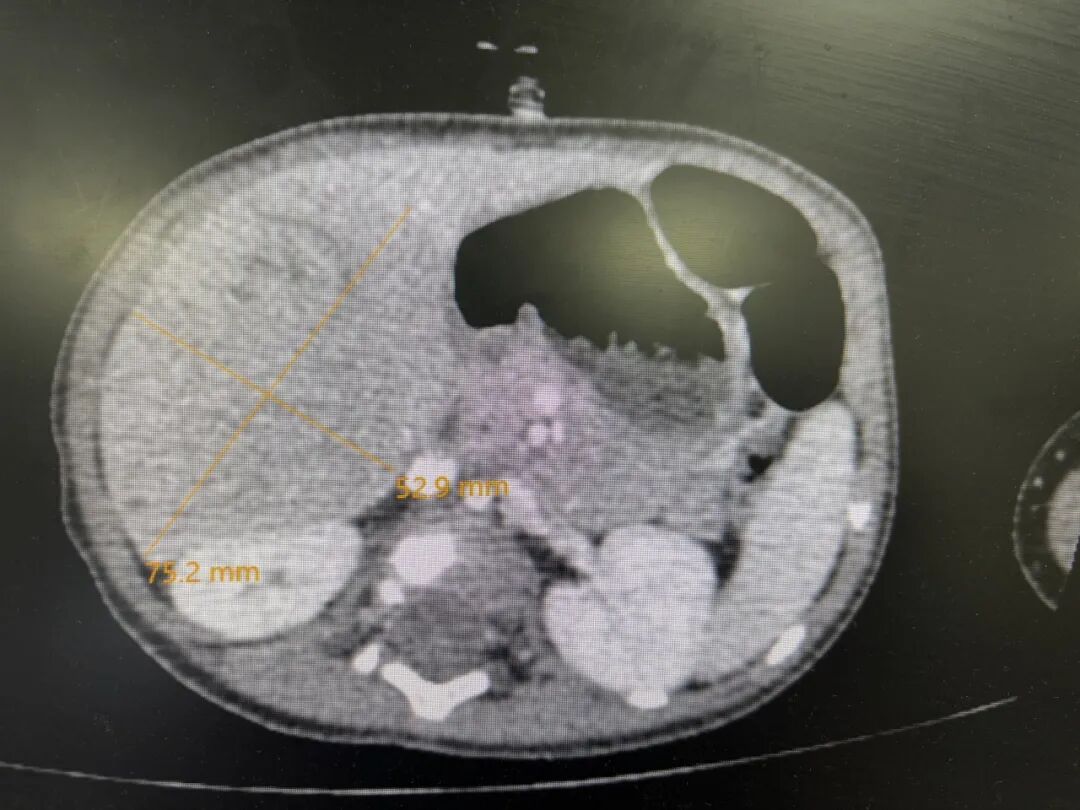

于是,爸爸妈妈带着妍妍找到武玉睿主任,在完善了各项检查后,基本可以明确,是肝母细胞瘤,最大径线达8厘米。肿瘤主要侵犯了肝第5段,6段和7、8段也有部分侵犯,肿瘤不止严重压迫正常肝组织和周围脏器,还与肝内的主要Glisson系统和肝静脉系统分界不清,如果贸然手术,要么需要扩大切除,这样就会丢失更多的肝组织;要么就不容易切干净肿瘤,因为初发肿瘤往往与肝内管道界限不清,强行手术的话肝内管道壁上容易残存瘤细胞,而且在肿瘤周围还有可能存在检查不出来的微小卫星灶,这都会增加术后复发的风险。经过权衡,武玉睿主任建议先给妍妍穿刺活检后做化疗,这样既可使瘤体缩小,又能使肿瘤建立假包膜,下次手术的时候,肿瘤与正常组织之间会有一个潜在间隙。而且化疗后,肿瘤周围可能存在的微小卫星灶一般也就被消灭掉了,所以化疗后再手术,肿瘤切除应该更彻底,复发率更低。经过了三轮的新辅助化疗,妍妍肝脏上的肿瘤比之前小了不少,于是,武玉睿主任决定给妍妍做根治手术。

化疗后